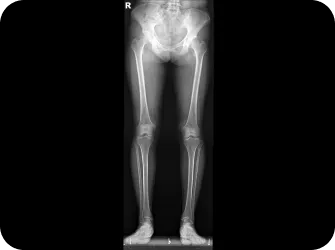

검사부터 다른 당당

“당당은 뼈만 보지 않습니다.”

근육과 근막의 정렬을 함께 진단하며, 풀 스파인 촬영을 통해 머리부터 모든 고관절, 발의 정렬까지 함께 파악하여 개개인에 맞는 전신 치료법을 설계합니다.

전신 엑스레이 검사

다리길이 엑스레이 검사